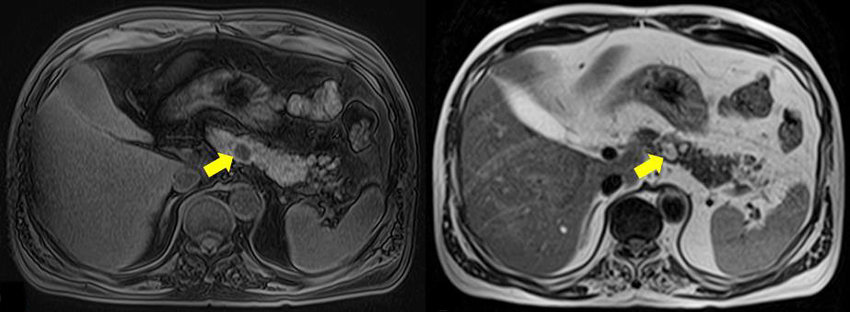

IRM

- La séquence T1 FS sans injection est la plus importante pour trouver les lésions !

- On les voit bien en T2 egalement (hyper T2)

- Attention en injecté: Tumeur Hyperartérielle plus difficile a voir au scan, Peut se noyer dans le pancreas spontanement hyperarteriel, sans washout

- Métas hépatiqes très hyperT2 (allure kystique) souvent

- L’arterielle est bien pour vour les métastases, hypervasculaires

- Mais le Must pour les Metastases c’est la diff car elles les captent fortement